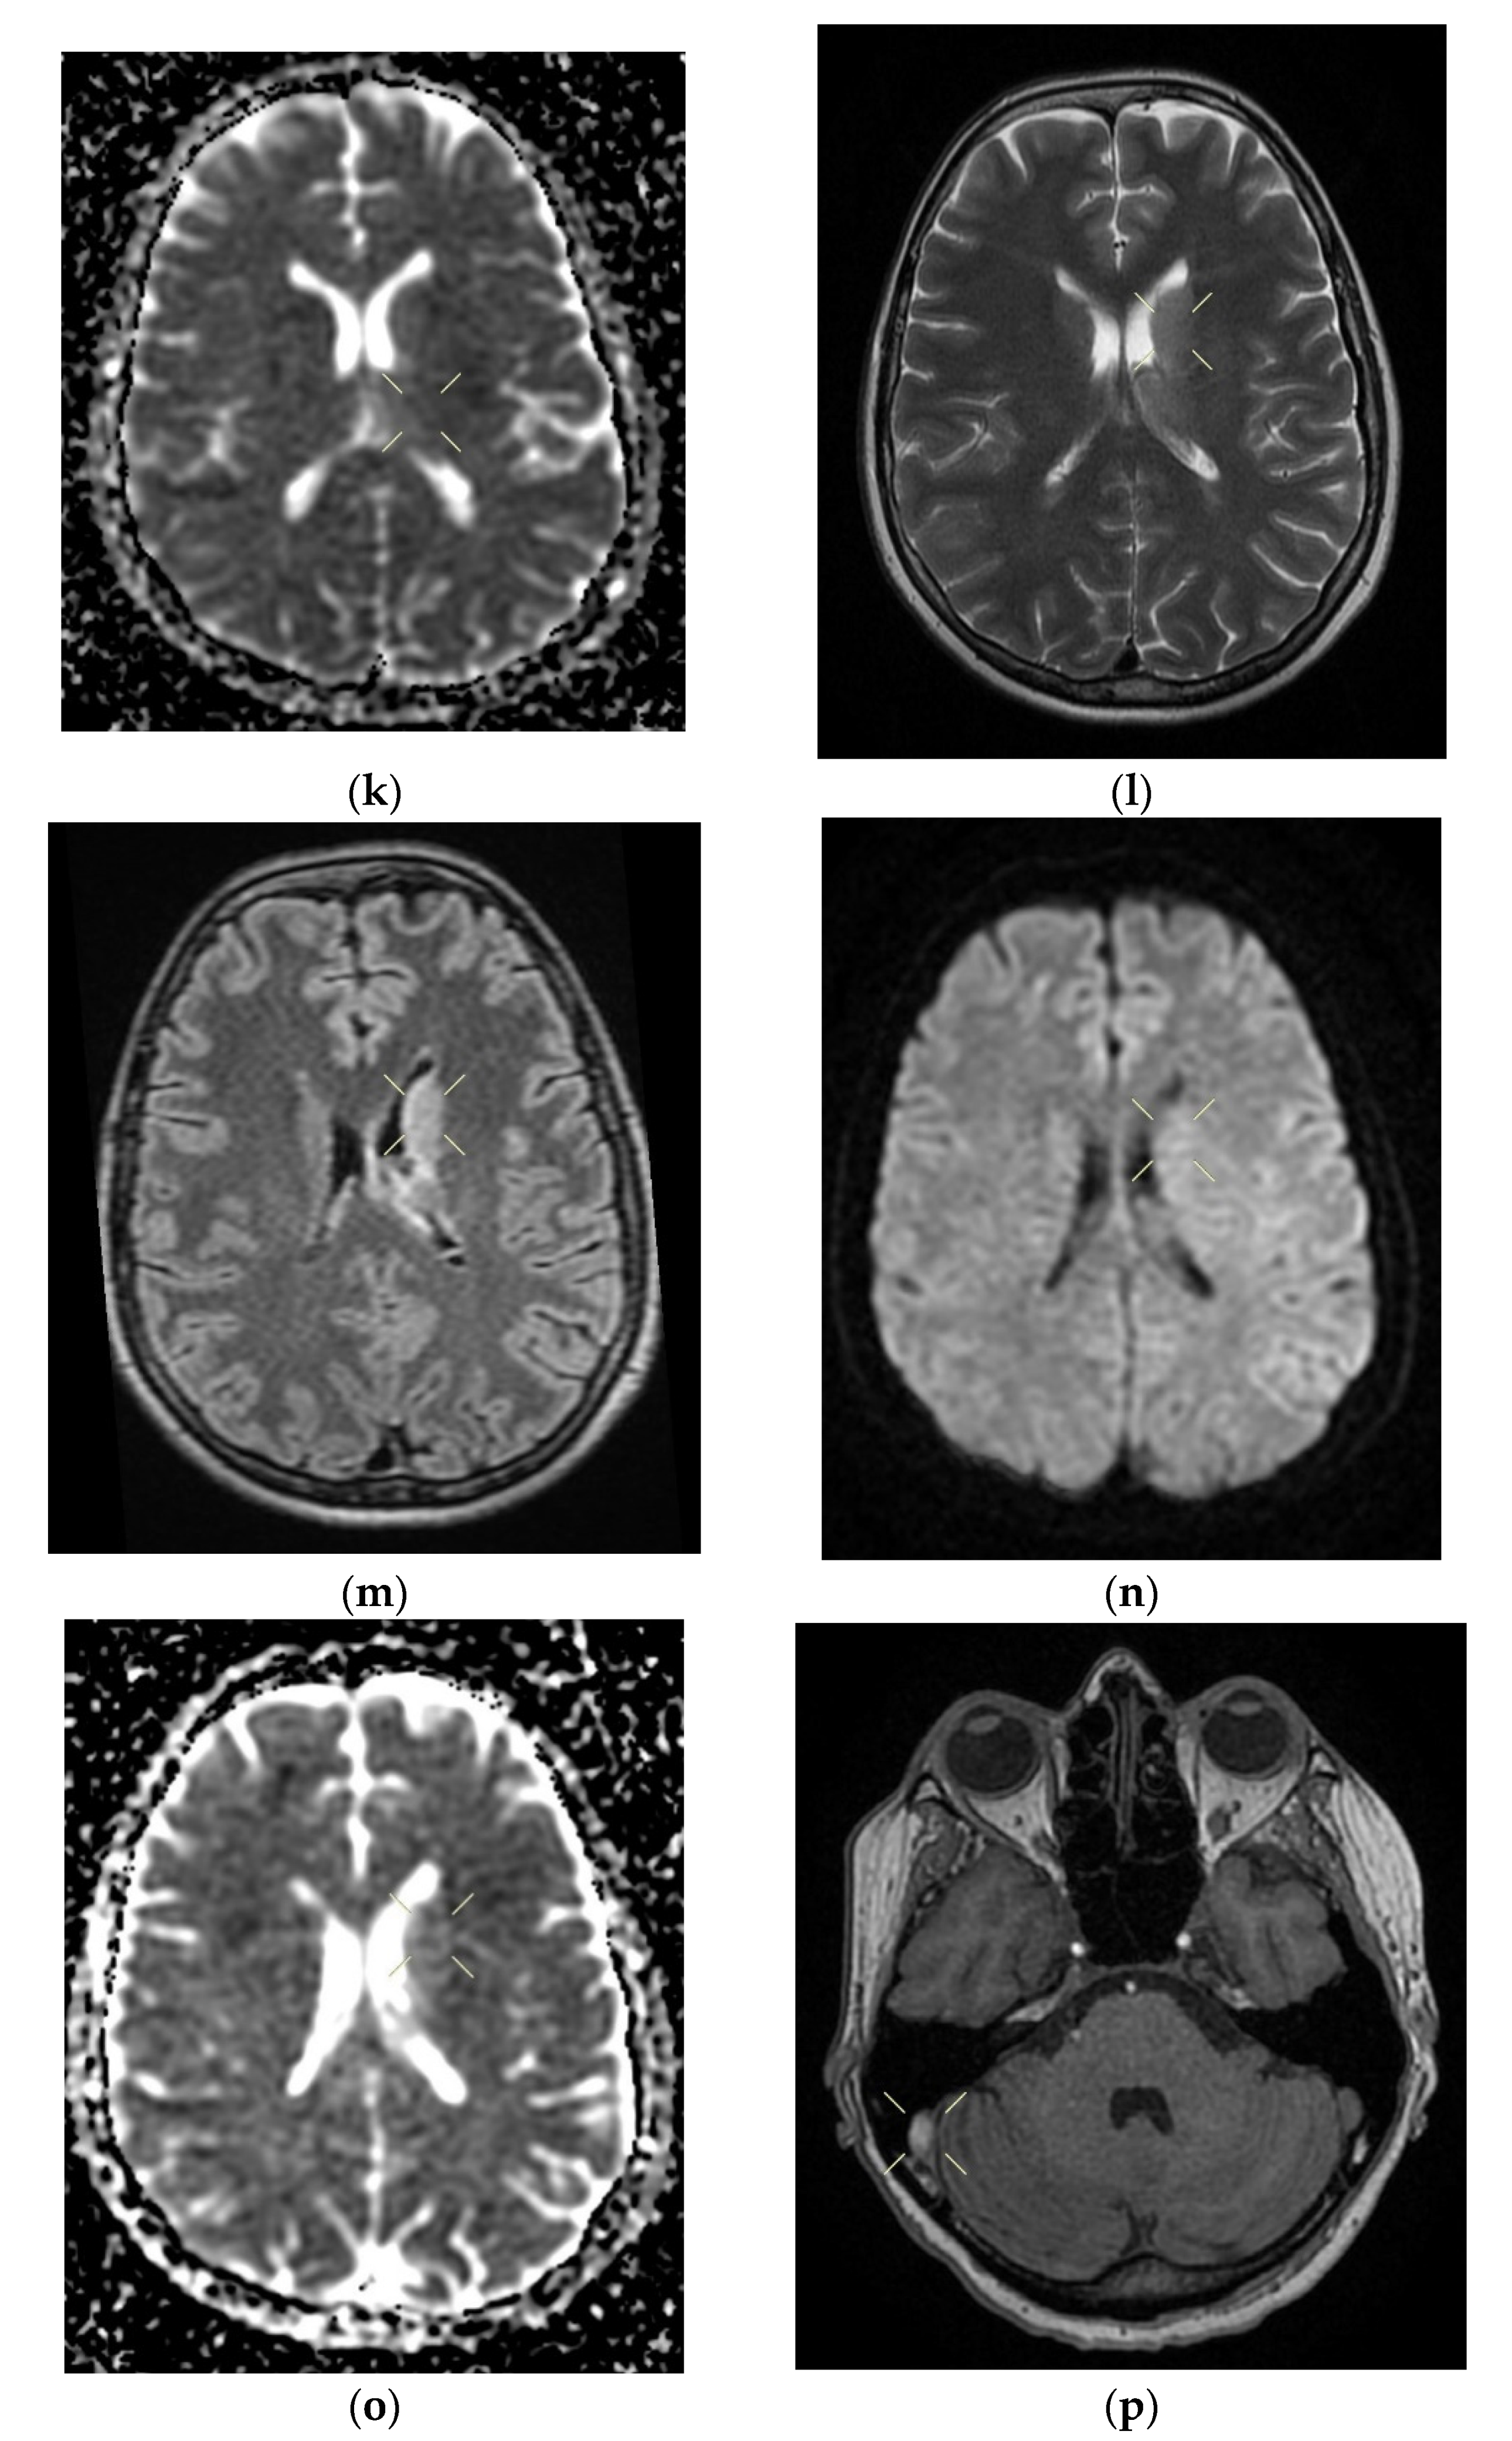

When discharged, the patient was conscious, cooperative, oriented in time and space, without stiffness in the back of the head, had no nystagmus, showed normal ocular motricity, denied diplopia, had possible deglutition for liquid and solid food, displayed symmetric facies, had no movement deficits, had no superficial tactile sensitivity or coordination disorders and showed a cutaneous plantar reflex with bilateral flexion. The images of the MRI can be seen below in Figure 4.

Figure 4. Native and contrast-enhanced cerebral MRI and angiography with arterial and venous sequencing, performed on the second day of hospitalization. The scan indicates thrombosis of the left parietal cortical vein associated with ipsilateral superior parietal subcortical venous infarction—(a) band in T2 and FLAIR hypersignal. (b) band in T2 and FLAIR hypersignal. (c) T1 hyposignal. (d) restrictive in diffusion coefficient. (e) restrictive in diffusion coefficient. (f) restrictive in diffusion coefficient with weak contrast enhancement. Demyelinating lesions are organized in the crown, radiated and parietal on the right side, most probably with an ischemic vascular sublayer. The native cranio-cerebral and post-contrast MRI examination with arterial and venous angiographic sequencing highlighted the following: normal pericerebral liquid spaces; a symmetric ventricular system, with normal dimensions; an area in the hypersignal band T2, and a FLAIR/iso-hypo signal T1, with restricted diffusion weighing, weak gadolinophilia, axial dimensions of about 9/16 mm, located subcortically and parietally on the upper left side; two millimeter focal points of the T2 and FLAIR hypersignal, with no diffusion restrictions or detectable contrast outlet organized in the crown, radiated and parietal subcortical on the right side, in the area adjacent to the dorsal horn of the VL; structures of the median line in the right position; orbits and orbital content without anomalies; paranasal sinuses with normal development and pneumatization; the absence of images evoking hemorrhagic accumulations or masses with a tumor sublayer; symmetrically disposed internal carotid arteries with normal trajectories and caliber; a normal bilateral carotid siphon with no position or extrinsic compression anomalies, with homogeneous intensity of the intralumenal signal; anterior and middle cerebral arteries that were normally detached from the internal carotid on both sides, without any areas of inferior longitudinal stenosis with an aspect within the normal limits; transverse and symmetric sigmoid sinuses, without lesions; the rest of the patient’s evaluable venous segments did not present any defect in the lumen signal.